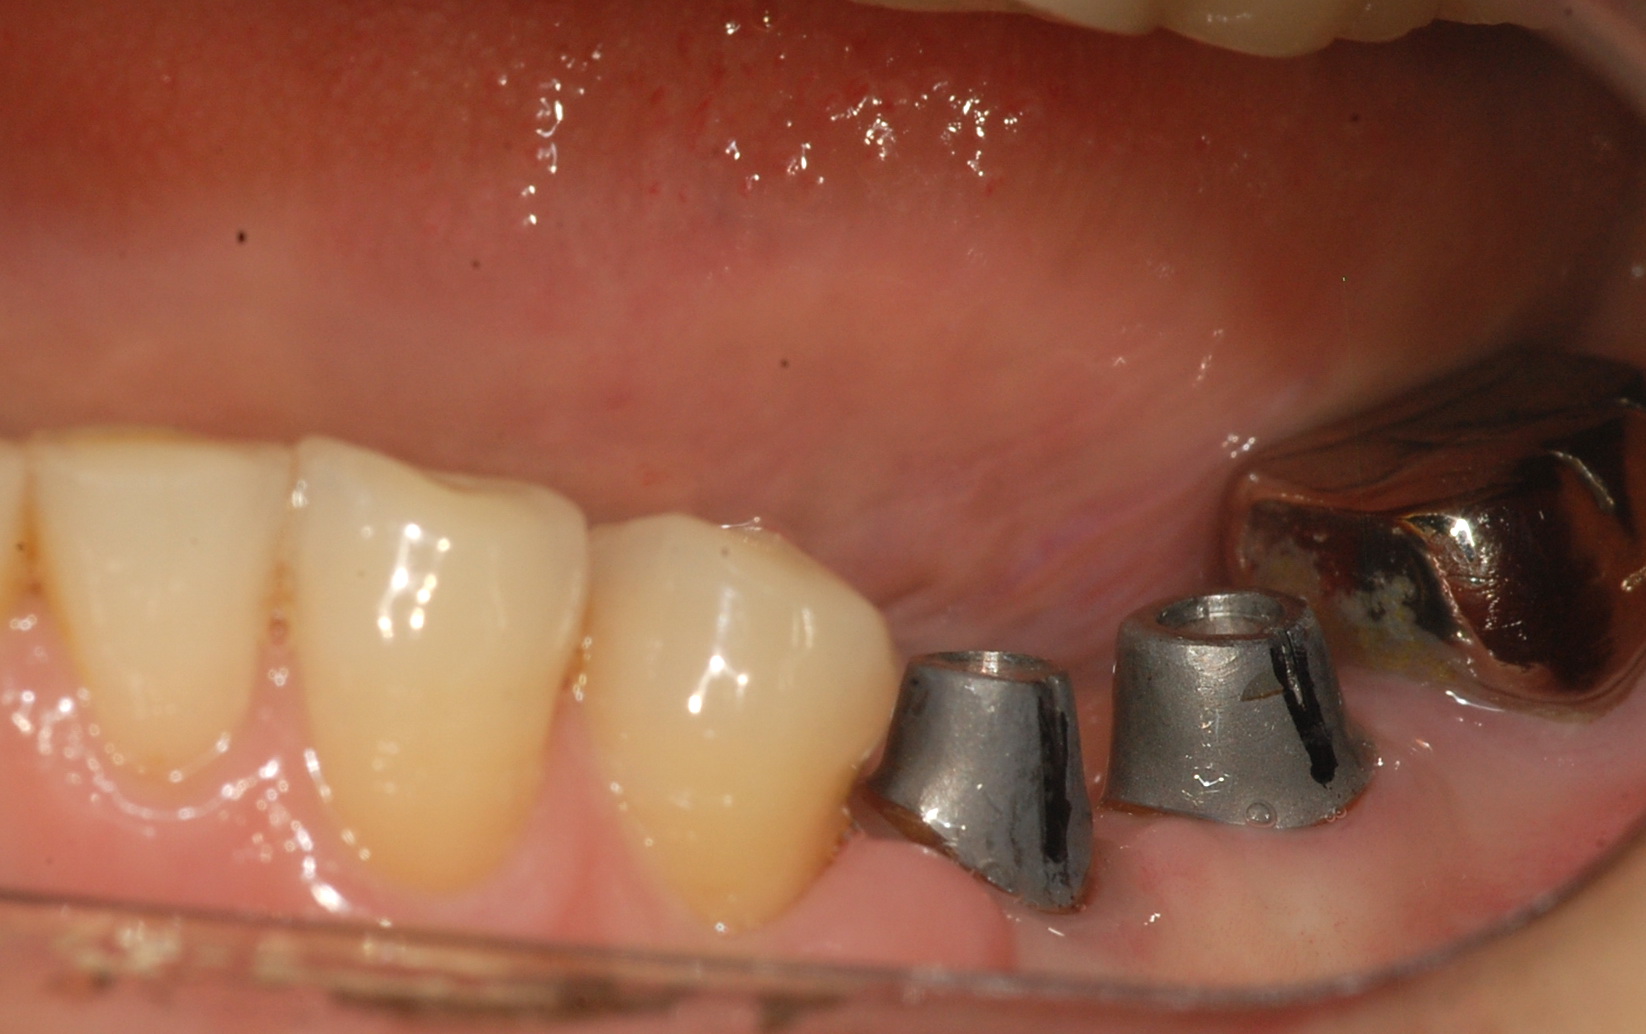

[임플란트] 제목 : 임플란트 지르코니아.

임플란트 지르코니아 보철